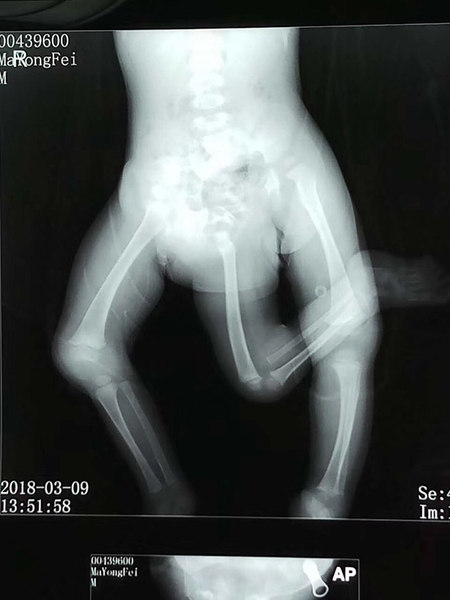

影像学检查。严晓慧供图

影像学检查。 严晓慧供图

飞飞仅11个月大,体重8公斤,患有先天性疾病,除了多了一条下肢,骨盆还有两个,消化系统、泌尿系统都存在畸形,同时还有先天性心脏病,右睾丸也并未在阴囊内正常发育。

11个多月大的男婴飞飞有三条腿。